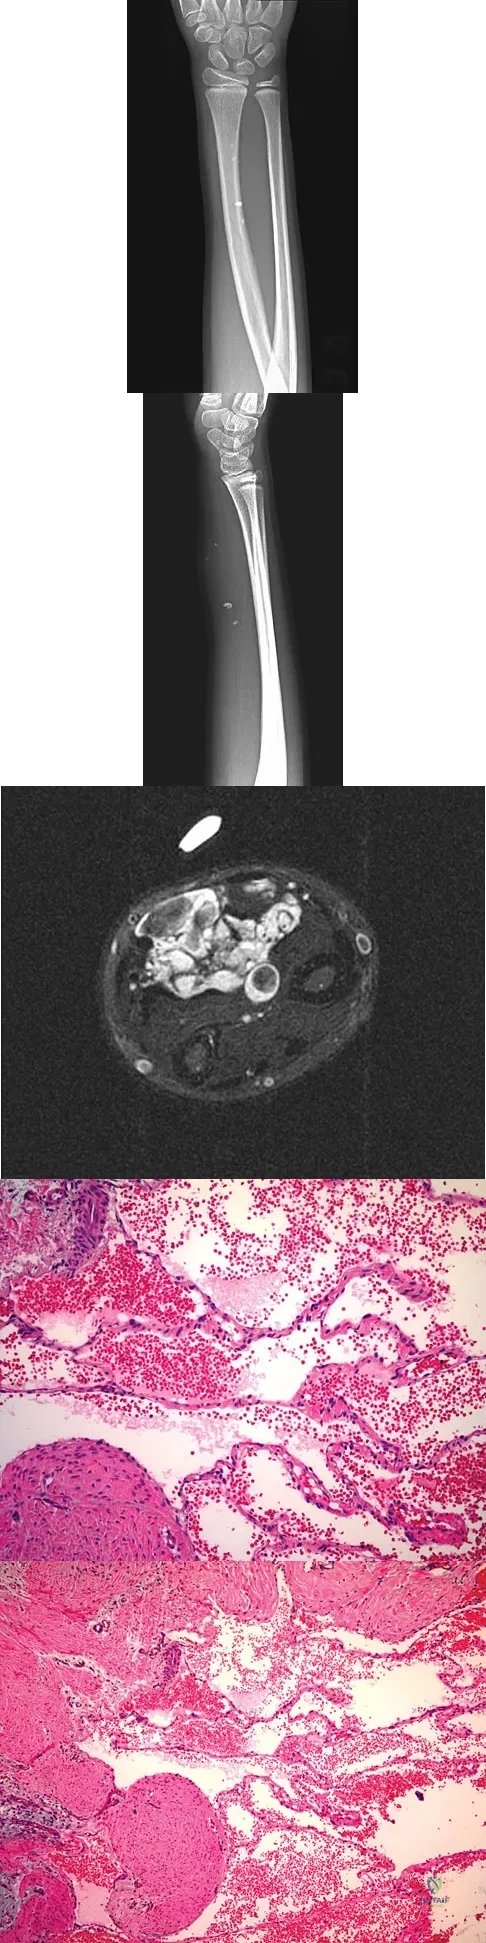

A 16-year-old boy has had thigh pain for the past several months. He denies any history of trauma. Examination reveals a large, deeply fixed, soft-tissue mass in the thigh. Laboratory results show an elevated erythrocyte sedimentation rate (ESR) and leukocytosis. A plain radiograph and MRI scan are shown in Figures 1a and 1b. Biopsy specimens are shown in Figures 1c and 1d. What is the most likely diagnosis?

Explanation